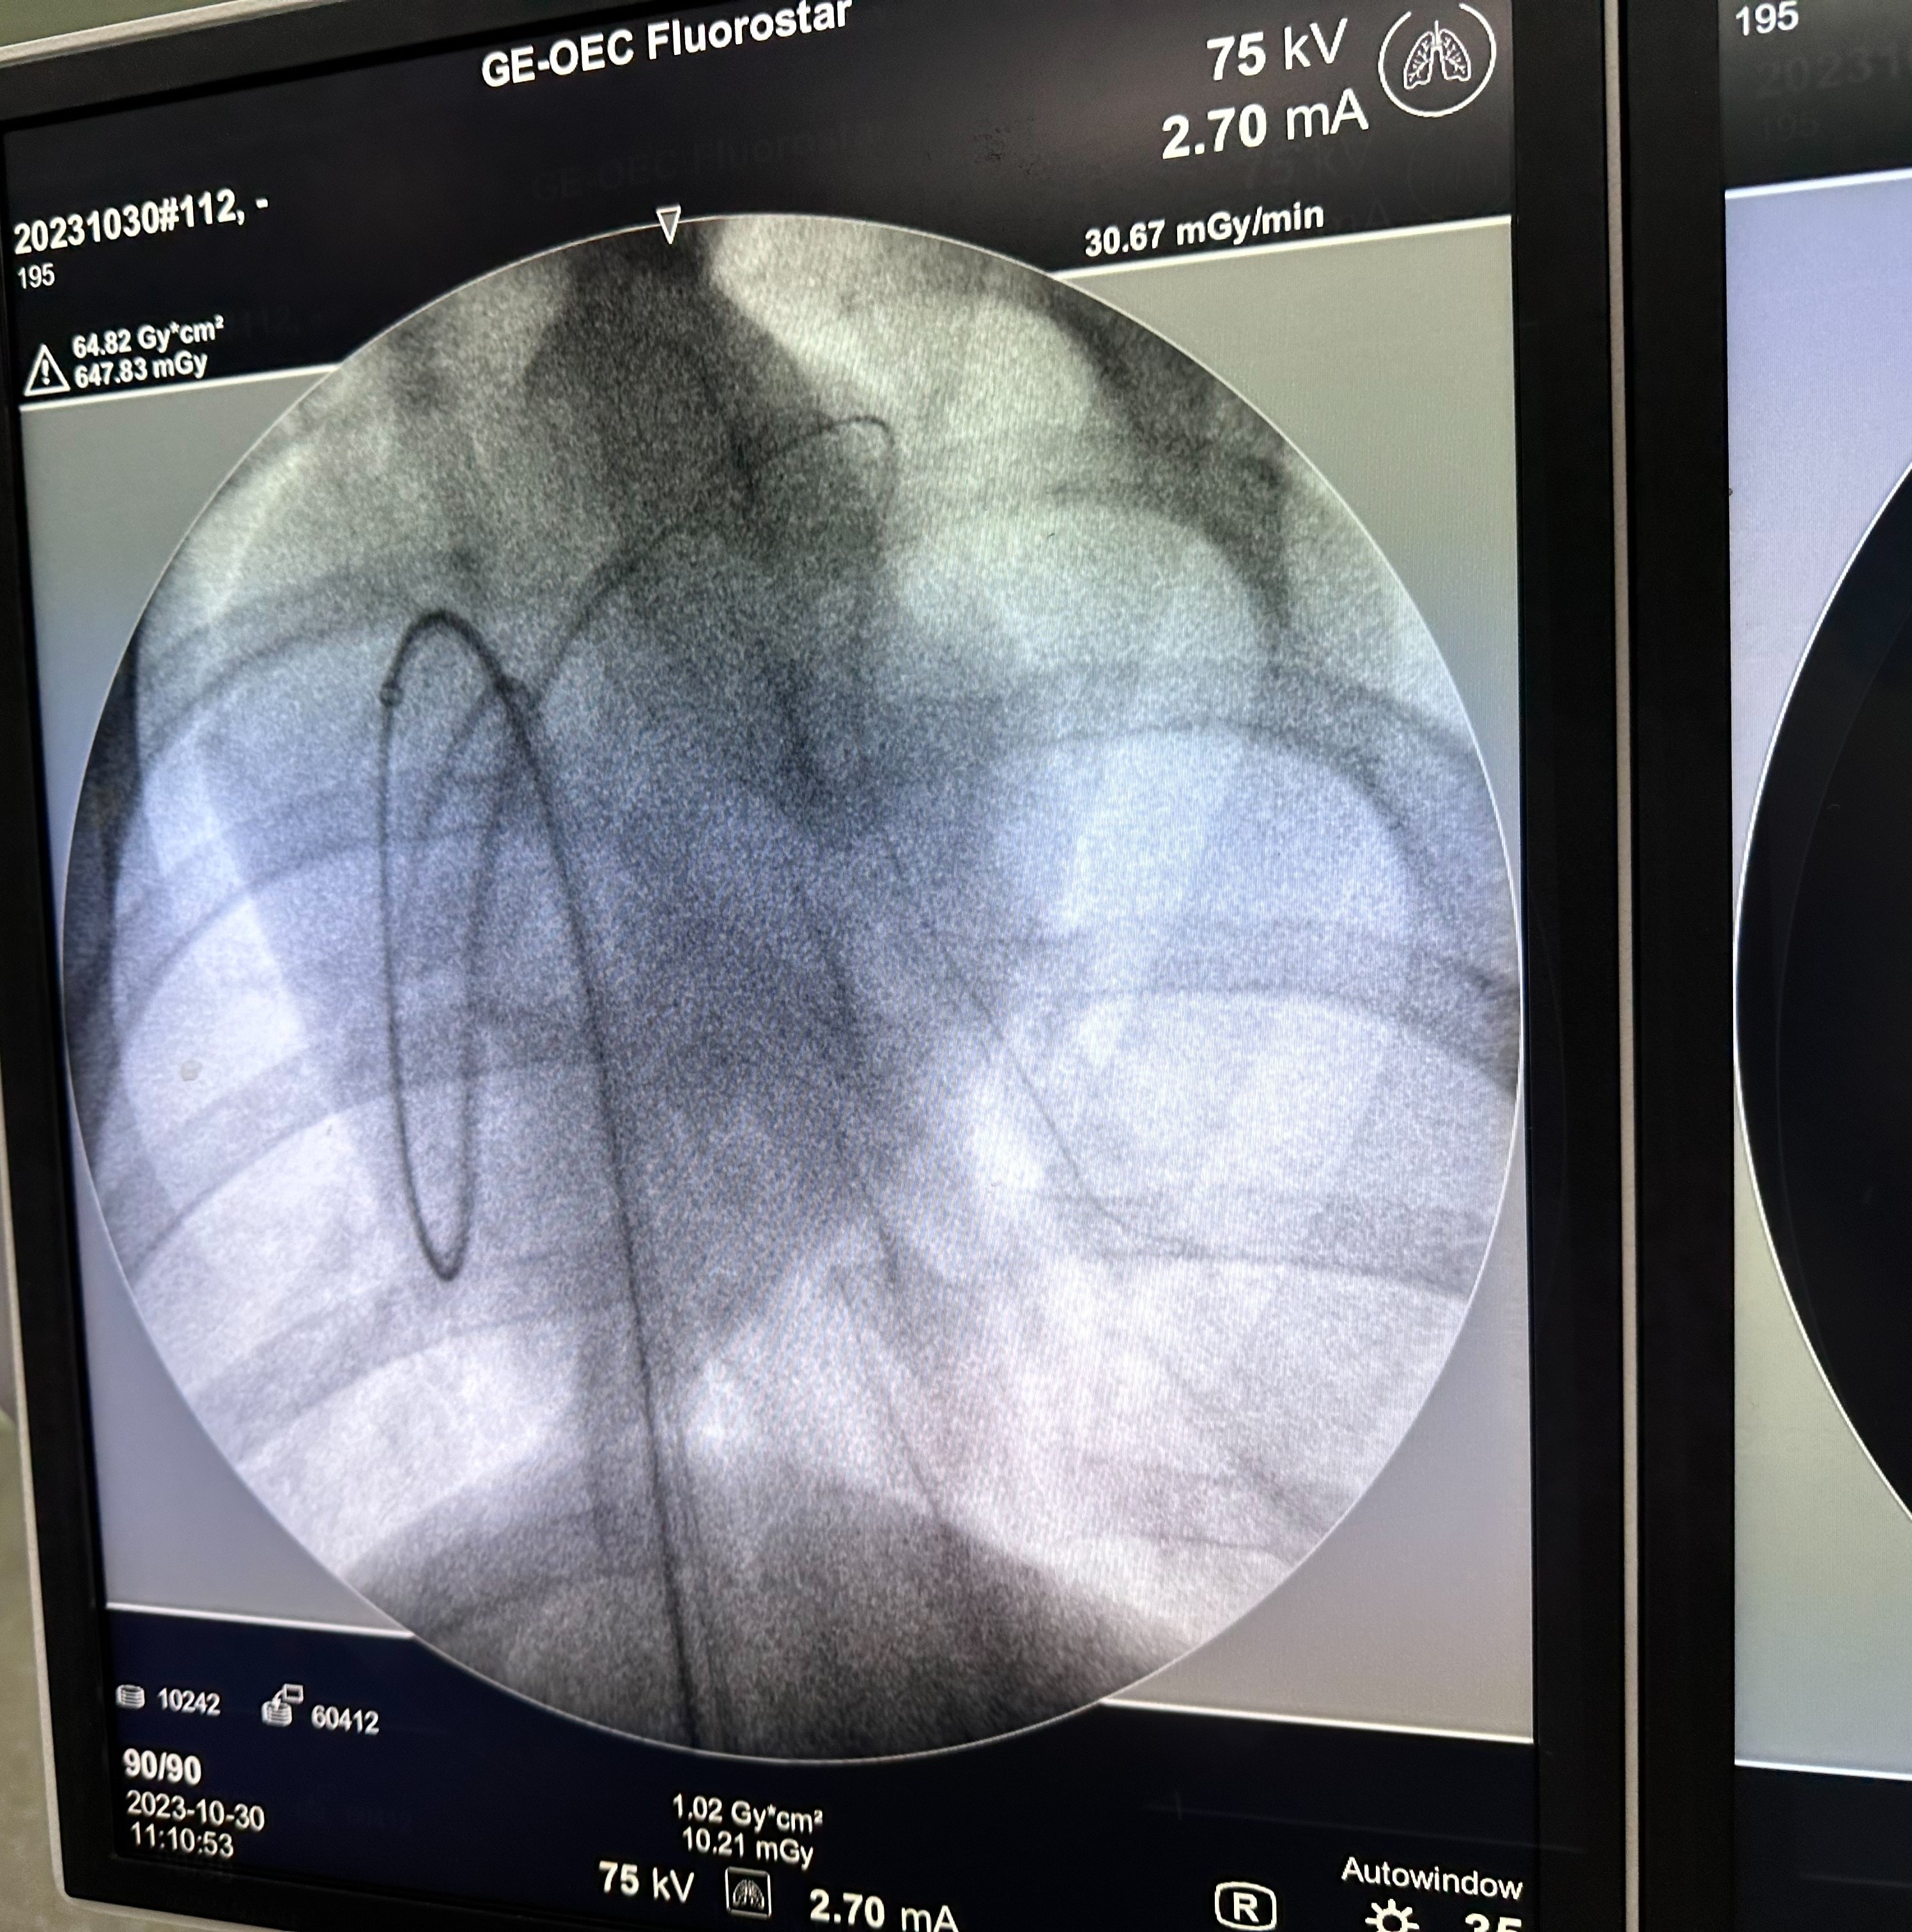

Experience 1 Photo Porcine Pulmonary Photo

SoundJet Medical Inc.

2023 - 2024 | Taiwan

Developed an automated needle epoxy injection system for catheter manufacturing, improving production precision. Participated in medical device prototype design and validation processes.